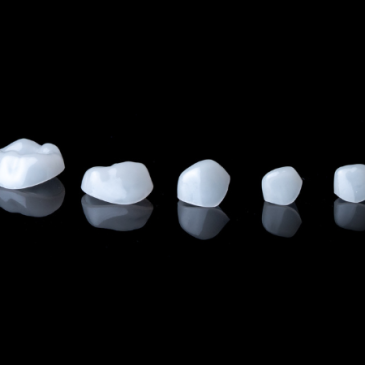

Un patient présente des triangles noirs inesthétiques au niveau antérieur. Grâce à la technique de composites interproximaux avec matrices BioClear BT Matrix, une solution esthétique et conservatrice est mise en œuvre pour fermer les triangles noirs et restaurer l’harmonie du sourire, tout en respectant la santé parodontale.… Lire la suite